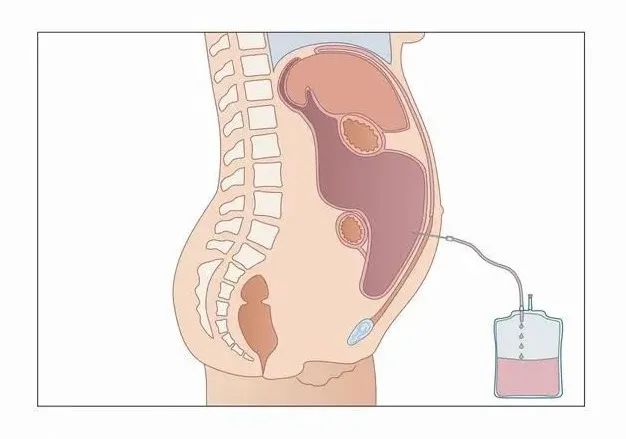

半个月前,65岁的高大伯被查出肝癌时已经是中晚期,去了几家医院都告诉他,因为瘤体较大,且生长位置不利于常规手术,只能肝移植。一家人在一筹莫展中来到了中国科学院大学附属肿瘤医院(以下简称国科大肿瘤医院),没想到找到了新的希望。 巨大肝癌患者的CT影像 高大伯是由女儿陪着来就诊的,接诊的是肝胆胰外科副主任张宇华。高大伯的女儿走进门诊时,眼睛肿肿的,一看就是刚哭过的样子,她拿出来一沓病历资料:化验单、影像学检查报告…… 来这里之前,高大伯一家跑了多家医院,得到的答案差不多:肿瘤大而且位置不好,需要切除的肝脏范围太大,剩余肝脏体积不足,无法行肝切除,建议肝移植。 “患者的右肝有两处肿瘤,最大的一处5厘米左右,紧贴门静脉右支,必须进行右半肝切除才能做到根治性切除。” 张宇华表示。 对高大伯一家来说,肝移植这个方案太渺茫,无论是治疗费用还是等候肝源,都让人感到绝望。 患者的肿瘤位于右半肝,从肿瘤切除的角度来说,可以通过行右半肝切除术来达到根治,但是高大伯的左半肝非常小,体积只有200多毫升,而术后至少需要400毫升以上才能维持人体的需要。这也就意味着,如果切除了高大伯的右半肝后,他的左半肝的功能无法满足人体需求,极有可能会造成肝功能衰竭、死亡的风险。 但是经过仔细的阅片后,细心的张宇华发现高大伯还是有手术的机会,张主任想到了一种快速使肝脏增大的技术,叫做联合肝脏离断和门静脉结扎二步肝切除术(ALPPS)。 通俗地来讲,这种手术方法就叫做“二步肝”。 简单来说,就是通过第一次开腹手术把肿瘤侧肝脏的门静脉结扎、再离断肿瘤侧与健康侧肝脏之间的肝实质,把两者之间的交通支离断。 也就是通过一定的手段,将有肿瘤的右肝和左肝“分离”。 经过这个操作后,肝脏的血流主要流向了健康侧的肝脏,也就是左肝,左肝快速长大后,达到手术要求,可以再次开腹手术切除病变侧肝脏。

通过微创,“分离”左右肝,养大健康肝脏

高大伯办理住院手续、进一步检查后,张主任团队精确的计算出他剩余左肝体积至少需要410ml,也就是说患者的肝脏至少需要增加200ml,才可以实施手术。

幸运的是,第一个阶段的手术非常成功,张宇华和团队通过5个5-10mm的小孔,把患者病变侧的门静脉右支进行结扎,然后通过离断左右半肝间的肝实质来分隔两侧肝脏。术后,高大伯没有出现任何并发症,第一次手术后3天就出院啦。

经过3周的休养,高大伯再次住院,经复查CT和三维重建,张宇华发现老高的剩余肝脏体积增加到了510ml,也就是说完全达到了手术的要求。

第二次手术中,高大伯的右侧肝脏也被顺利切除。

术后通过肝胆胰外科护理团队的精心护理,高大伯术后5天已经拔除所有引流管康复出院。

“传统的二步肝手术创伤大,并发症多,很多病人因此止步于第一步。腹腔镜技术应用于ALPPS,两步手术都通过微创来完成,明显减少了患者的创伤,在第一步手术中,胆漏、出血等并发症发生率特别低,从而保证了第二阶段手术的顺利进行。”